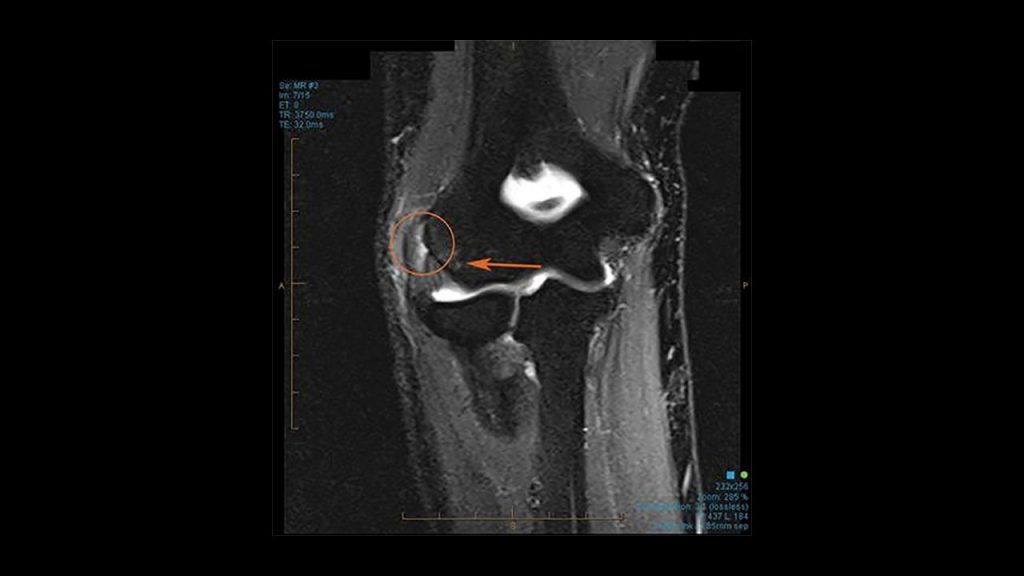

Η έξω επικονδυλίτιδα χαρακτηρίζεται από πόνο ή κάψιμο στην έξω επιφάνεια του αγκώνα και μειωμένη δύναμη δραγμού (πιασίματος). Η διάγνωση γίνεται συνήθως μόνο με τον κλινικό έλεγχο, με δοκιμασίες φόρτισης των εκτεινόντων, όπως έκταση του καρπού υπό αντίσταση ή μέγιστη κάμψη του καρπού. Σε αμφίβολες περιπτώσεις ο νευρολογικός έλεγχος δύναται να αποκλείσει το σύνδρομο παγίδευσης του κερκιδικού νεύρου, το οποίο συχνά μιμείται την έξω επικονδυλίτιδα. Η μαγνητική τομογραφία δεν είναι απαραίτητη, αλλά δείχνει αυξημένο σήμα στην περιοχή έκφυσης των τενόντων.